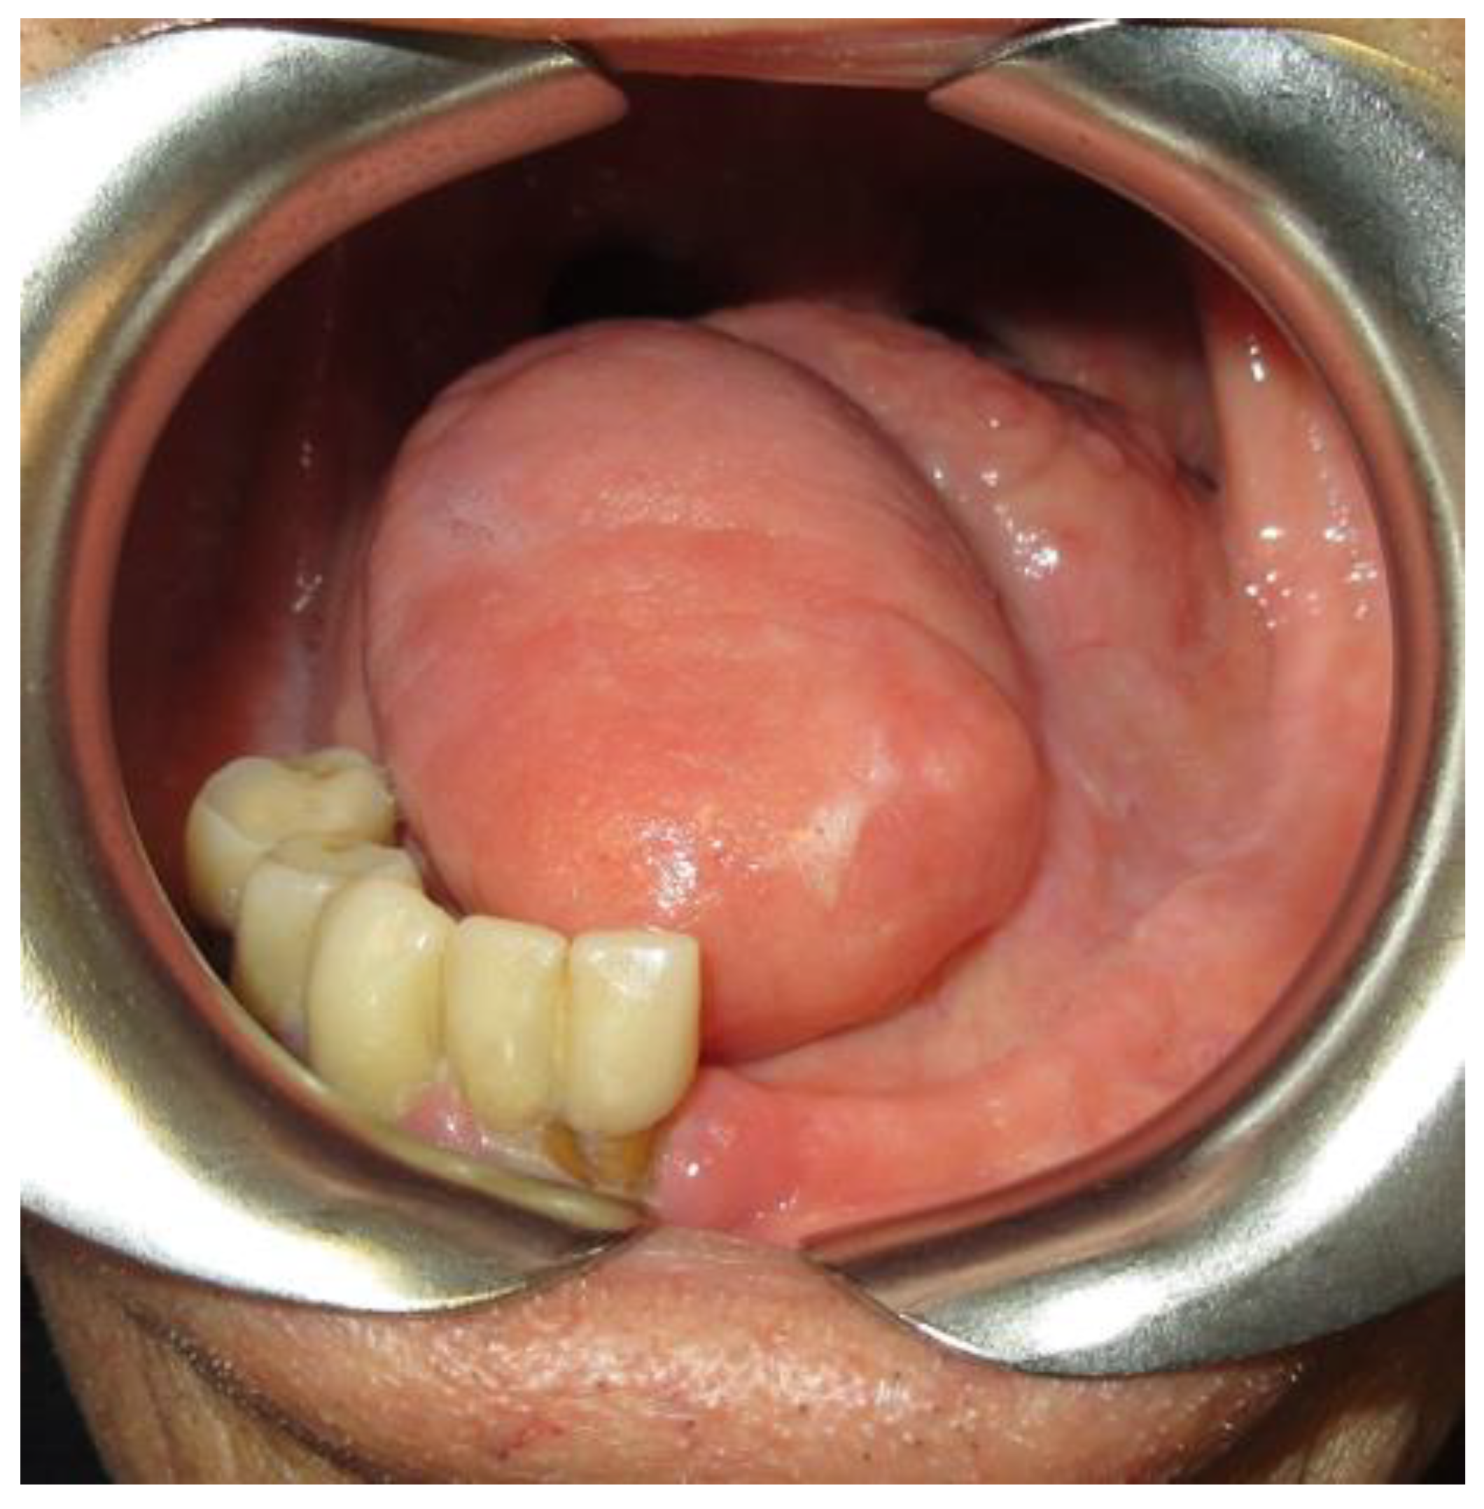

2.4. Soft Tissue Condition

2.4.1. Tongue Mobility

2.4.2. Keratinized Gengiva

- Brauner, E.; Valentini, V.; De Angelis, F.; Jamshir, S.; Visca, A.; Romeo, U.; Tenore, G.; Pompa, G.; Di Carlo, S. Gingival hyperplasia around dental implants in jaws reconstructed with free vascularized flaps: A case report series. J. Int. Dent. Med. Res. 2018, 11, 1–7. [Google Scholar]

| SOFT TISSUE | LOW TONGUE MOBILITY | |

| DEFICIENCY/ABSENCE OF KERATINIZED GENGIVA IN FUTURE IMPLANT INSERTION ZONE | ||

| SUFFICIENT KERATINIZED GENGIVA IN FUTURE IMPLANT INSERTION ZONE | ||

| NORMAL TONGUE MOBILITY | ||